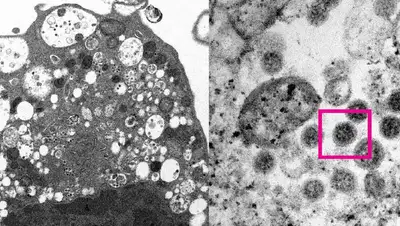

Ученые университета Гонконга опубликовали электронную микрофотографию «омикрон-штамма», передает Zakon.kz.

Изображение варианта коронавируса «омикрон-штамма» получено при помощи электронного микроскопа, сообщается в заявлении исследователей, поступившем в распоряжение РИА Новости.

Ученые медицинского факультета, включая специалистов в области патологии и вирусологии, смогли сделать электронную микрофотографию клетки (Vero E6) почки обезьяны после заражения вариантом SARS-CoV-2 «омикрон». Университет обнародовал изображение при малом и большом увеличении.

Китайские ученые пояснили, что при малом увеличении на микрофотографии видно повреждение клеток с набухшими везикулами, содержащими маленькие черные вирусные частицы. Микрофотография с большим увеличением показывает агрегаты вирусных частиц с шипами в форме короны на их поверхности.